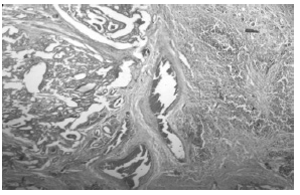

Рис. 2. Сочетание фолликулярного рака щитовидной железы с аутоиммунным тиреоидитом Хашимото. Окраска гематоксилином и эозином. X 400.

Рис. 3. Сочетание фолликулярного варианта папиллярного рака щитовидной железы с аутоиммунным тиреоидитом Хашимото. Окраска гематоксилином и эозином. X 400.